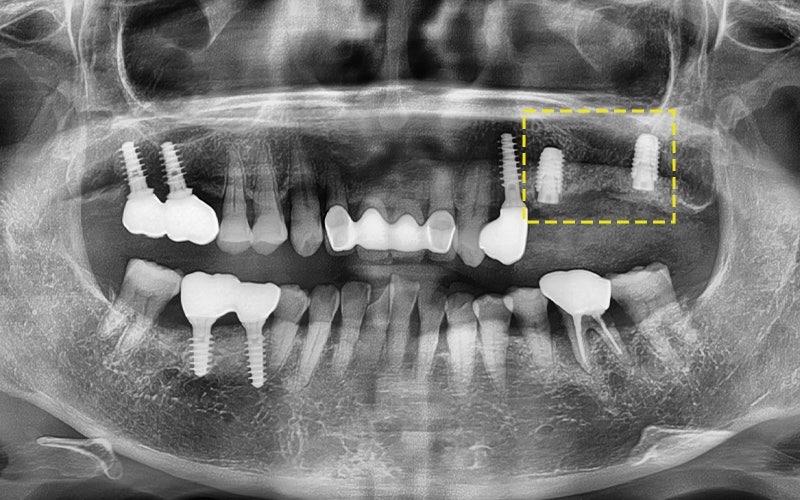

This patient said that it had been only about 3 years

since the implant was placed at another dental clinic.

The implant was physically fractured

(the screw body broke),

and gum inflammation also occurred,

creating a serious situation that even affected nearby teeth.

The photos above show the implant that was actually removed.

The screw body had snapped due to metal fatigue,

and around the head there was a large amount of tartar and inflammation.

The surrounding gum bone had melted away,

which eventually led to extraction of the adjacent tooth as well.

In the end, the implant had to be placed again,

and overall reconstruction was needed.